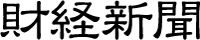

【国際学会で日本から世界に発信】クリフム出生前診断クリニック 夫 律子院長がFMF World Congressで胎児脳研究を発表

クリフム出生前診断クリニック(所在地 : 大阪市天王寺区、 https://fetal-medicine-pooh.jp )の夫 律子院長【順天堂大学医学部産婦人科学講座 客員教授・聖マリアンナ医科大学産婦人科学講座 客員教授・大阪大学大学院医学系研究科 招へい教授・米国Wayne 州立大学産婦人科 特命教授】は、2025年7月にプラハ(チェコ共和国)で開催された胎児医療分野の世界最高峰の学会「FMF World Congress」において、胎児脳の最先端研究について招聘講演を行いました。日本から唯一の招聘は同クリニックの研究が世界的に高く評価されていることを示しています。

招聘講演

FMF(The Fetal Medicine Foundation, 胎児医学財団)は、胎児医療分野で世界的に著名なKypros Nicolaides教授が1990年にイギリスで設立した組織で、同分野における最重要機関です。毎年開催される「FMF World Congress」は、世界中の胎児医療エキスパートが集結し、最新の研究成果と技術について講演・議論する場として位置づけられています。

今回の第22会プラハ大会では、5日間にわたり最前線で活躍する約170人の専門家による講演と約3200名の参加者との活発な学術交流が展開されました。日本から招聘された専門家は夫 律子院長のみでした。